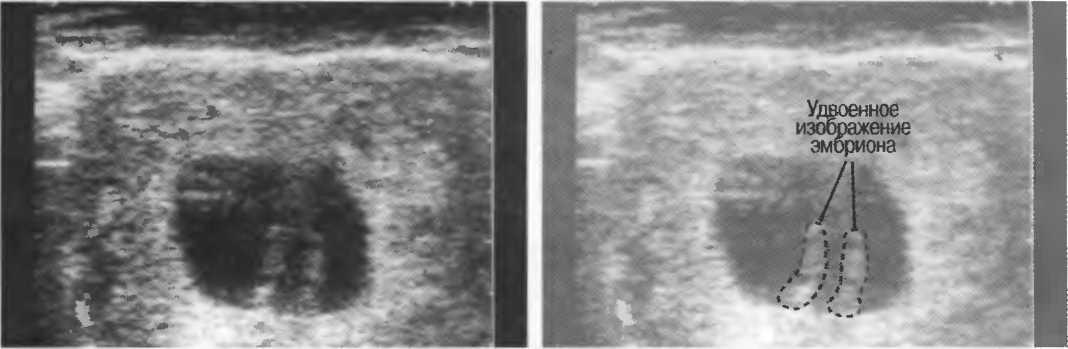

Стенка брюшной полости

Выраженная подкожножировая клетчатка и мышцы могут рассеивать ультразвук, делая визуализацию более глубоких структур менее отчетливой. Иногда мышечный слой удваивает изображение, создавая иллюзию разделения: при этом может иметь место ложная диагностика (например, двойни). Всегда необходимо проводить полипозиционное исследование под различными углами при подозрении на наличие артефактного изображения (рис. 18).

Рис. 18. Мышцы, особенно стенки брюшной полости, могут иметь эффект выпуклых линз. Такая беременность на ранних сроках выглядит, как беременность двойней, так как эффект линзы прямых мышц живота вызывает удвоение изображения плодного яйца. На продольных срезах второе плодное яйцо не определяется.